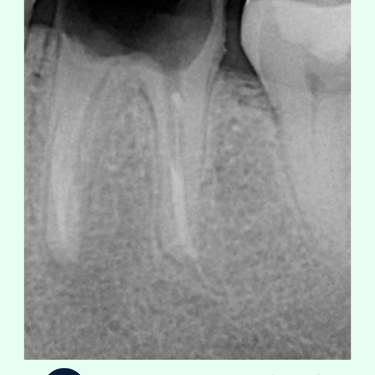

Radiografías: Se toman radiografías para evaluar el estado de los conductos radiculares tratados previamente y el hueso circundante. Las radiografías ayudan a detectar cualquier signo de reabsorción ósea, abscesos o fracturas radiculares.